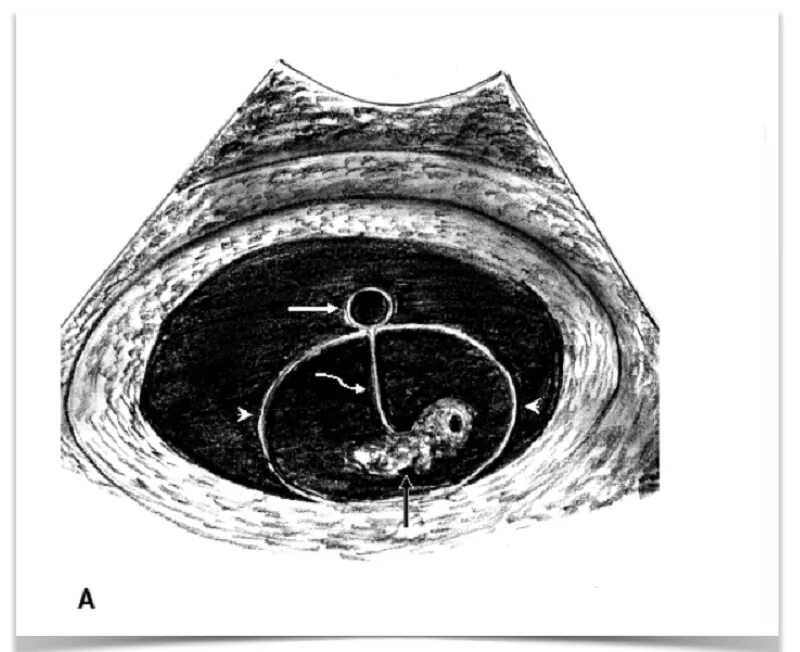

Плодное яйцо желточный мешочек